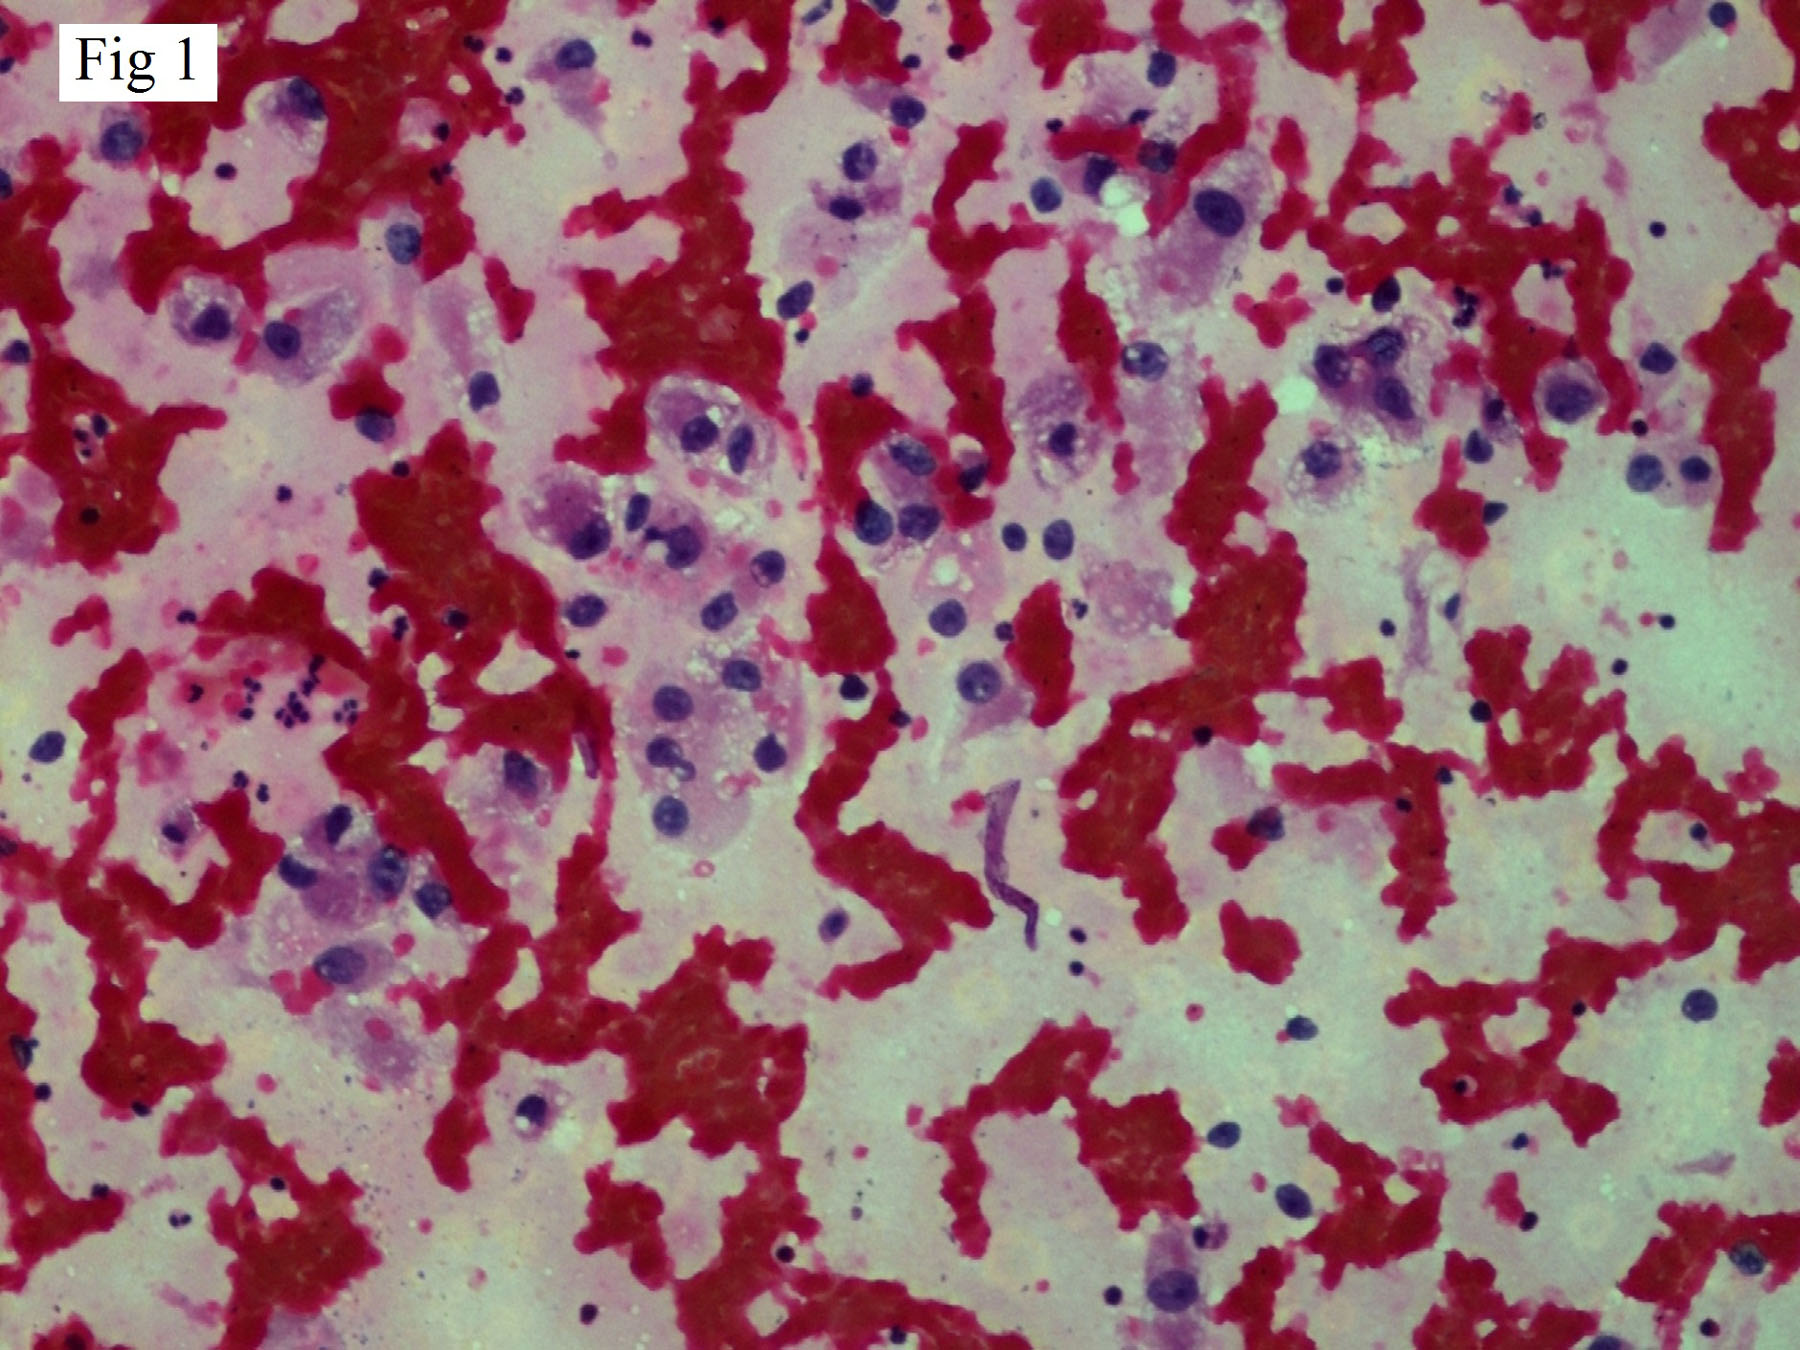

A 51-year-old male presented with a solitary, painless irregular swelling over chin for 3 months. On examination the swelling was firm, measuring about 3x2x1cm. No other significant past history was given at this point. Computed Tomography (CT) scan of face and neck showed a solitary well defined heterogenously enhancing mass arising from skin and subcutaneous tissue measuring 27x17x15mm in size. Radiological impression was of a primary skin tumour or metastatic tumour. FNAC was done and slides stained with May Grunwald Giemsa (MGG), Haematoxylin and Eosin (H&E) Papanicolaou (Pap) stain. Smears prepared from the swelling were moderately cellular and showed predominantly large singly scattered cells with few clusters of poorly cohesive cell. Cells showed an abundant pale, foamy/vacuolated cytoplasm with central to eccentric nucleus, 0-2 nucleoli and bland chromatin [Table/Fig-1]. In some cells, nuclei were totally or partially stripped of cytoplasm leaving bare nuclei [Table/Fig-2]. No intranuclear cytoplasmic inclusions were noted. Based on smear examination, a diagnosis of “clear cell malignant tumour, possibly metastatic RCC” was made. On second visit of patient detailed questioning was done with review of past records. History of nephrectomy 11 years back was elicited. Wide excision of tumour was done and sent for histopathology. On histopathological examination it was confirmed as metastatic RCC-clear cell type showing the typical clear cells arranged in solid sheets with a delicate branching vasculature [Table/Fig-3,4]. Immunohistochemistry for CK AE1/AE3 and CD10 was strongly and diffusely positive but was negative for S-100 and HMB 45.

FNA smear showing clear cells in poorly cohesive clusters and scattered singly. Cells have finely vacuolated cytoplasm with nuclear atypia [H&E 200X].